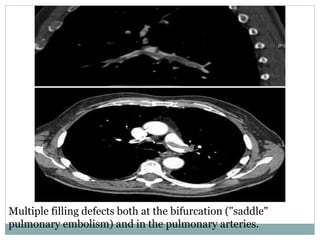

Multiple filling defects both at the bifurcation ("saddle"

pulmonary embolism) and in the pulmonary arteries.